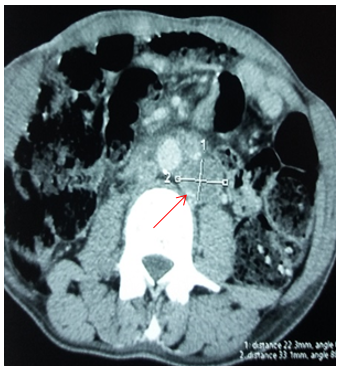

Figure 6. Bone metastase.

Figures 3, Figure 4, Figure5, Figure 6: The most common metastatic sites (CT scans): Node involvement (Figure 3), lung metastases (Figure 4), liver metastase (Figure 5), bone metastase (Figure 6).